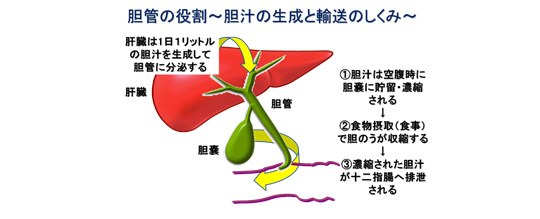

疾患での役割 [ ] 胆石症 [ ] 最大25%の人間が、、、およびで構成されたを持つ。 急性胆のう炎では、胆のうが浮腫などにより肥大しますが、慢性胆のう炎では胆のう壁が分厚くなり、胆のう自体のサイズは萎縮していきます。 写らない場合でも、胆嚢を映し出す造影剤があって、それを経口的、あるいは経静脈的に与えることにより胆嚢を映したり、内視鏡的逆行性胆管造影法によって、中にある石をみつけます。